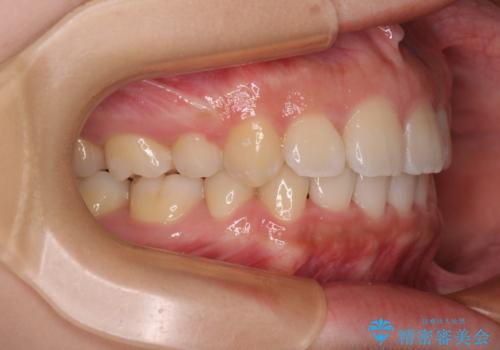

- 前歯の出っ歯と口元の閉じにくさを気にして来院された患者様です。

口元を積極的に引っ込めるために、上下左右の小臼歯4本を抜歯することとしました。